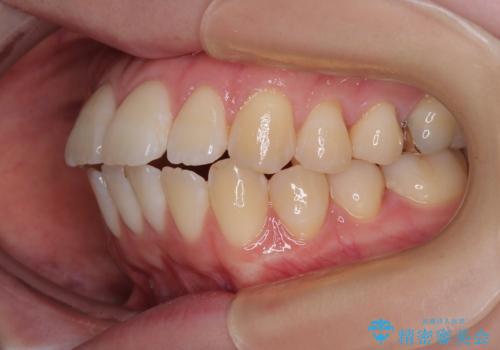

- くちばしのように飛び出した前歯を気にして来院された患者様です。

上下左右の第一小臼歯4本を抜歯して、ワイヤー装置にて矯正治療を行うこととしました。

舌の突出癖により、口元が突出しているだけでなく、上下前歯が非接触となっておりました。

舌のトレーニングをしっかりと行っていただくことで、2年を切って治療を終えるとともに

、上下前歯を接触させることができました。